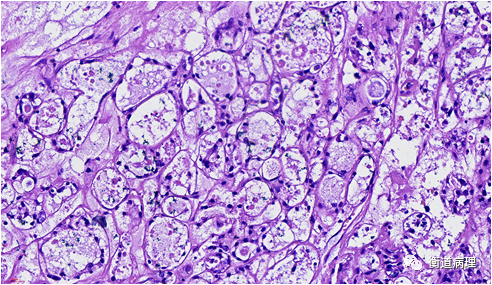

【衡道丨干货】卵巢透明细胞癌中的一招鲜——树莓小体_医学界-助力

卵巢丨透明细胞癌_手机搜狐网